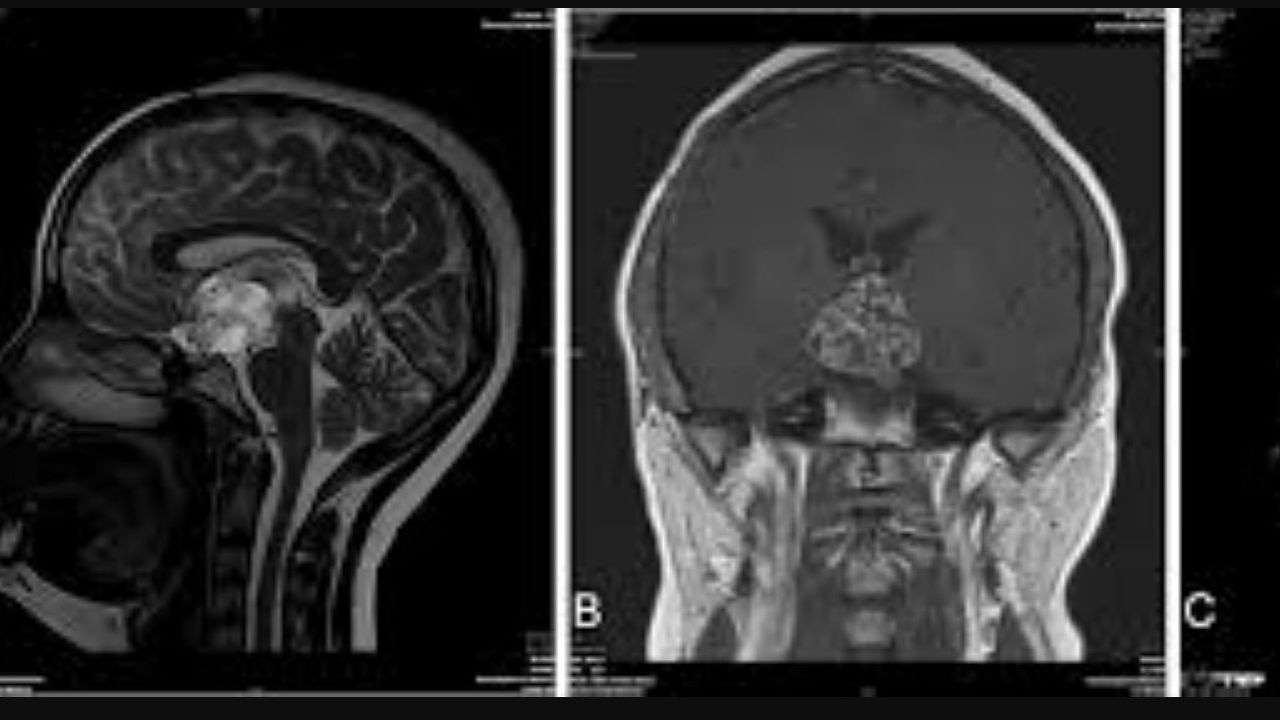

T2a Ve, tıbbi görüntüleme tekniklerinde kullanılan bir terimdir ve özellikle MRI (Manyetik Rezonans Görüntüleme) taramalarında önemli bir yere sahiptir. Bu tür taramalar, beyindeki ve omurilikteki farklı doku türlerini ayırt edebilmek için kullanılır. T2a sinyalleri, sıvı birikimlerine ya da lezyonlara dair önemli ipuçları sağlayabilir. Bu nedenle, T2a Ve sinyallerinin analizi, birçok hastalığın erken teşhisi ve doğru tedavi planlaması için kritik öneme sahiptir.

T2a Ve, birçok nörolojik ve metabolik bozukluğun tespitinde kritik bir araçtır. Tümör gibi ciddi durumların yanı sıra demiyelinizan hastalıklar ve nörodejeneratif hastalıkların erken tanısı için de önemlidir. Örneğin, T2a Ve'nin yüksek olduğu bölgelerdeki parlaklık, glioma gibi malign tümörlerin erken evrede saptanmasına yardımcı olabilir. Ayrıca, T2a sinyalleri kronik hastalıklarda çeşitli aşamaların izlenmesine de katkıda bulunur. Bu bağlamda, T2a değerlendirmesi sayesinde tedaviye yanıtın ölçülmesi ve hastalığın ilerleyişinin izlenmesi sağlanabilir. Beyin, omurga ve diğer organlardaki değişikliklerin izlenmesinde yaygın olarak kullanılır.

T2a Ve Flair hiperintens odaklar, beyin görüntülemede sıklıkla karşılaşılan bulgulardır. Çoğu zaman multipl skleroz, vasküler parkinsonizm veya bazı migren türlerinin teşhisinde önemli bir rol oynarlar. Beyinde herhangi bir patoloji belirtisi gösteren bu odaklar, klinikte belirli semptomlar veya rahatsızlıklar ile ilişkilendirilebilir, bu nedenle erken teşhis ve doğru değerlendirme oldukça önem taşır.

Flair hiperintens odaklar, beyin MRI'ları üzerinde çok net görülebilseler de, her hastada benzer klinik sonuçlara ulaşılmaz. Sağlıklı bireylerde veya yaşlanma ile ilişkili değişikliklerde de benzer görünümler olabilir. Bu nedenle, T2a Ve Flair hiperintens odaklarının değerlendirmesi dikkatle yapılmalıdır.

Flair hiperintens odakları tespit etmek için kullanılan görüntüleme teknikleri arasında özellikle MRI önemli bir yere sahiptir. MRI, beyin dokularının detaylı bir haritasını çıkararak bu odakların nerede ve nasıl oluştuğunu anlamamıza olanak tanır. Ek olarak, görüntüleme teknikleri arasında T1, T2 ve Flair sekansları, farklı doku özelliklerini ve hastalık belirtilerini daha iyi kavramak için kullanılabilir.